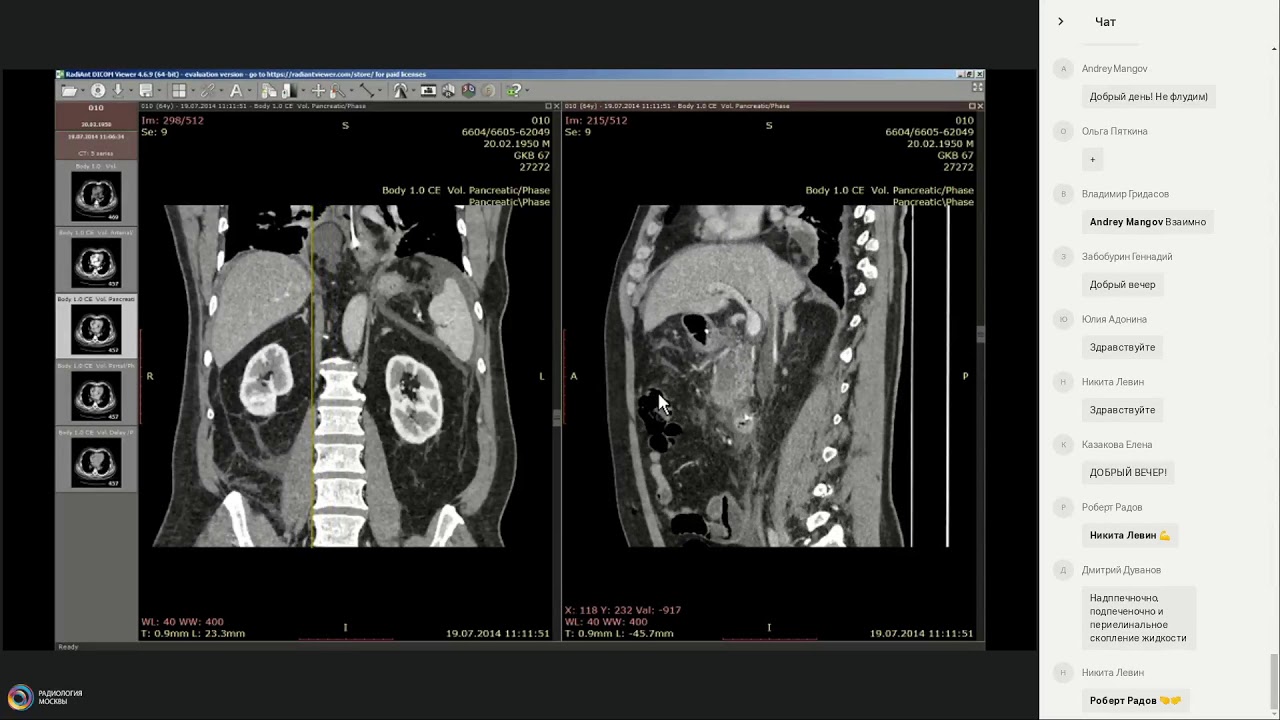

Хронический панкреатит. Вопросы терапии

04 апреля 2024 г. в 16:00 состоится вебинар «Хронический панкреатит. Вопросы терапии».

В своем докладе “Хронический панкреатит. Вопросы терапии” д.м.н., профессор Эмилия Прохоровна Яковенко рассмотрит вопросы- что такое панкреатит, расскажет о различных классификациях ХП, этиологии, причинах и факторах влияющих на возникновение ХП, патогенезе заболевания, клинических проявлениях и симптоматике, разберет очень подробно диагностику и даст практические советы по решению данной проблемы и лечению. В своем докладе лектор актуализирует место и действие ферментных препаратов в лечение ХП.

Техника написания заключений КТ  Острый и хронический панкреатит